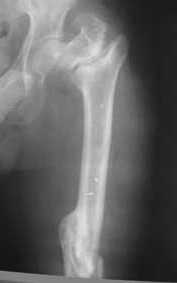

Re: Ложный сустав вертельной области бедра.

Возможно, пример (в приложении) поможет Вам определиться с выбором тактики лечения (у нашего пациента, кроме тугого ложного сустава вертельной области, сложная деформация н/3 бедренной кости; т.к. это не имеет значения к обсуждаемой теме - оставил "за кадром"). Как Вы видите, мы в данном случае не вводили чрескостные элементы в зону установки имплантата. При отказе от наложения опоры на таз (кстати, она не обязательно может быть громоздкая спицевая; арки со стержнями-шурупами, введенными в крыло подвздошной вполне достаточно) "не удивляйтесь", если опора со стержнями-шурупами, введенными в вертельной области в скором времени дестабилизируется, возникнет воспаление мягких тканей у чрескостных элементов. Такая опора "имеет на это право": нагрузка конечности от вершины дистального фрагмента до кончиков пальцев ляжет на нее. А двух-трех введенных рядом стержней-шурупов, как их не разноси от фронтальной плоскости, в данном

случае явно недостаточно для адекватной фиксации. + для того, чтобы выбрать оптимальные чрескостные элементы для промежуточной и дистальной опор, можете воспользоваться атласом